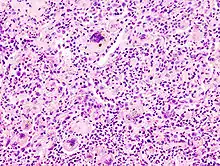

- Zytologisch: Polymorphie, basophiles Cytoplasma, erhöhte Kern/Plasmarelation

- Nukleär: Polymorphie, Polychromasie, Hyperchromasie, Aneuploidie, (vergrößerte) Nukleolen, vermehrt Mitosen, atypische Mitosen, erhöhter Proliferationsindex (Ki-67 = MIB-1).